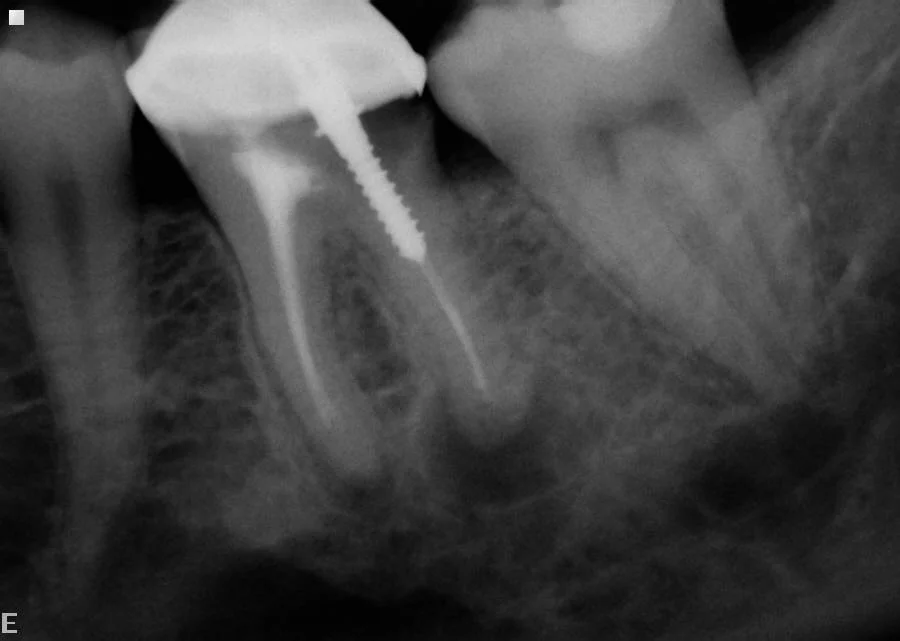

After: Re-root treatment